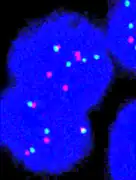

Fluorescence in situ hybridisation

FISH can be used to measure the number of copies of the gene which are present and is thought to be more reliable than immunohistochemistry.[47] It usually uses chromosome enumeration probe 17 (CEP17) to count the amount of chromosomes. Hence, the HER2/CEP17 ratio reflects any amplification of HER2 as compared to the number of chromosomes. The signals of 20 cells are usually counted.

This cell displays 2 signals of HER2 (red) and 3 signals of CEP17 (green)

Two signals that are closer to each other than the signal diameter count as one.

One of these signals is too faint, and is presumably debris.

Cells with only one type of signal are excluded from the count.

Overlapping cells are also excluded from the count.

A yellow signal counts as one red and one green (which are overlapping)